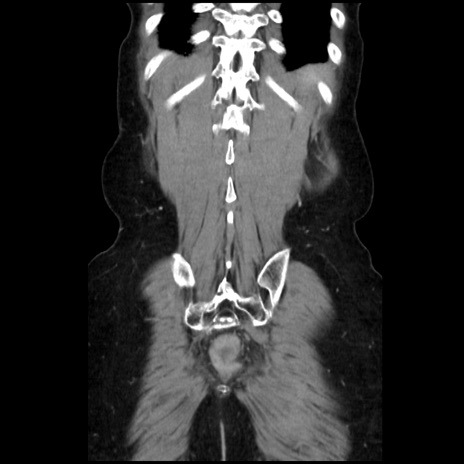

症例32(冠状断像)

【症例】40歳代 女性

【主訴】上腹部痛、嘔気・嘔吐

【現病歴】約9時間前頃から急に上腹部痛、嘔気、嘔吐が出現。改善しないため救急要請。

【既往歴】子宮頚癌(広汎子宮全摘術、放射線療法)、腸閉塞

【身体所見】腹部:平坦、軟、腸雑音亢進、上腹部を中心に腹部全体に圧痛あり。

【データ】WBC 8400、CRP 0.03